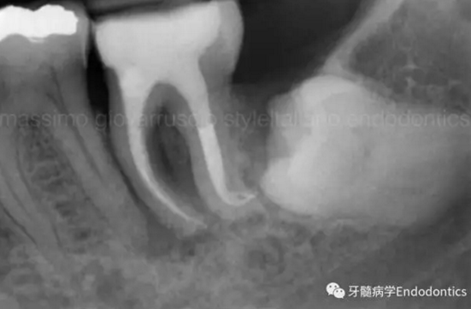

圖4.根尖孔通常比10號K銼大,因此感到任何阻力時可能是因為根管的彎曲或不規(guī)則。因此,有效的建立可重復的引導通道的方法應是使用10號K銼逐步擴大開放根管,此時也將產生臺階或根管堵塞的可能性降到最低。

圖5.探查時銼不能向根尖方向用力,因為形成臺階的風險會顯著增加。如果銼的尖部從未卡入根管壁,是不可能形成臺階的。

圖6.術后X線片顯示在根管機械預備后保留了原始的根管解剖形態(tài)結構。冠方預敞和探查保證了對整個根管解剖形態(tài)結構的保護。